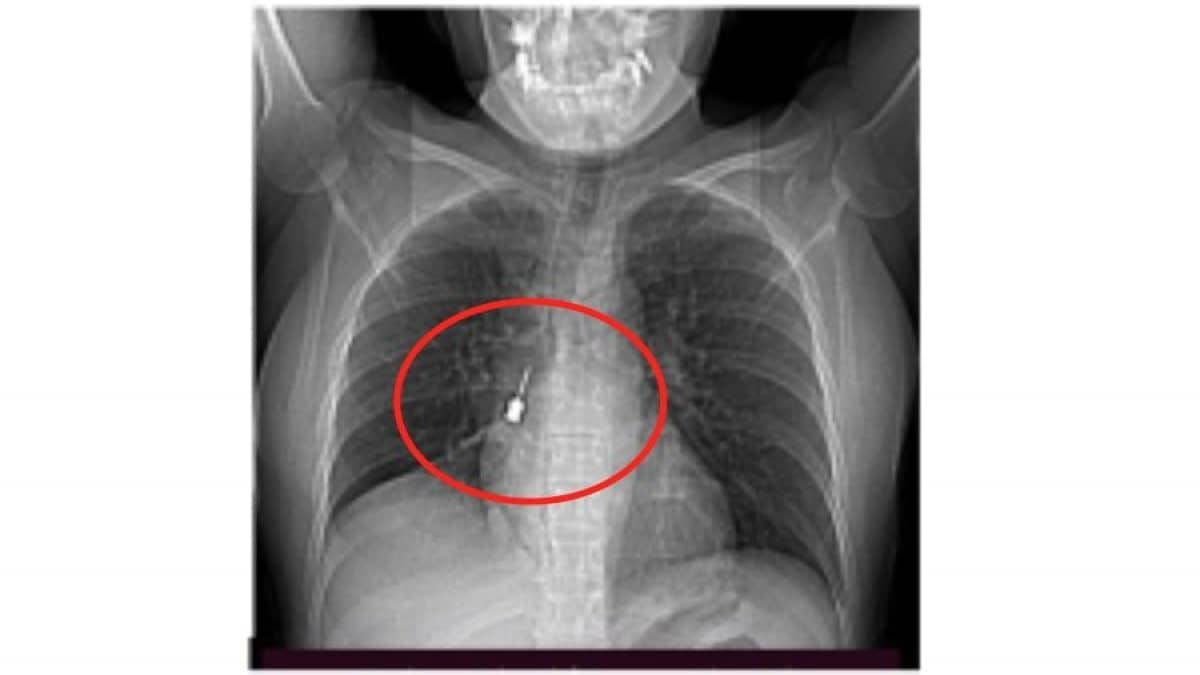

Come si vede dalle foto diffuse dallo stesso ospedale reggino, la Tac infatti mostrava chiaramente la presenza di un corpo estraneo metallico pericolosamente incastrato nel bronco lobare inferiore del polmone destro. Allo stesso tempo i medici si sono accorti anche di “un concomitante pneumomediastino” ossia la presenza di aria nello spazio compreso fra i due polmoni. Una situazione molto delicata e pericolosa che ha spinto i sanitari a disporre una immediata operazione chirurgica d’urgenza.